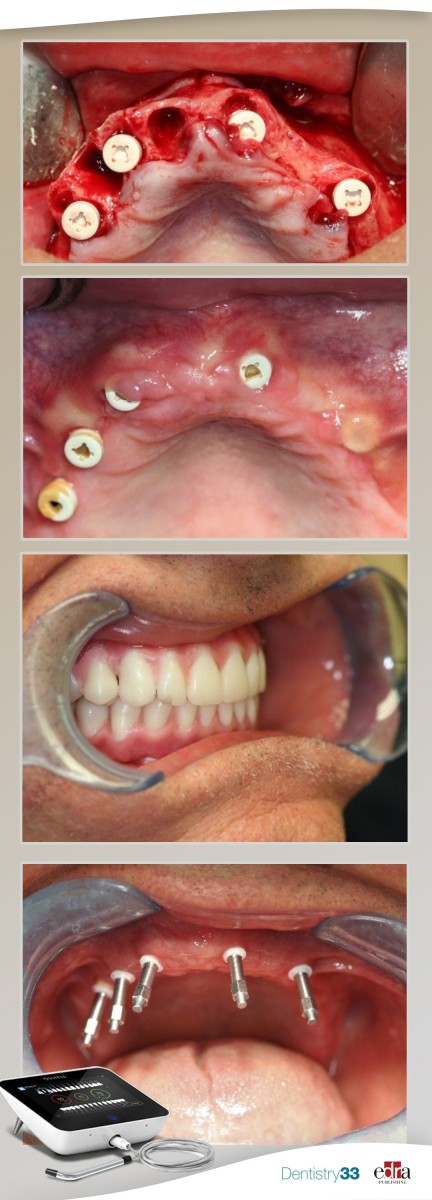

A 59-year-old male presented partially edentulous with severe collapse in the vertical dimension of occlusion. Most teeth were periodontally involved or fractured at the gingival level. The periodontally involved teeth had mobility type II with moderate to advanced bone loss and gingival recession (Figure 1, above).

Only three mandibular teeth were present with no teeth remaining in the mandibular left quadrant and moderate to advanced vertical bone loss (Figure 2). A cone beam CT scan was obtained and reviewed to assess bone levels, anatomy as well as critical anatomical structures in the areas of planned implant placement (Figure 3).

The patient had difficulty wearing removable appliances, had a severe gag reflex and wanted a metal free fixed solution to replace his teeth. Alternative treatment options were presented including overdentures on four ceramic implants. The patient opted for maxillary and mandibular fixed full arch screw-retained prosthetics using zirconia ceramic implants. A two-phased treatment plan consisting initially of full arch extractions, immediate implant placement in both arches and soft –reline immediate dentures for both arches.

Four months post-surgery the implants were uncovered, and the soft tissue above the implants’ cover screws was removed with a diode laser where needed. The smart pegs specifically designed for the implants were screwed into the implants and stability measurements were made using resonance frequency analysis technology. This modality has been well proven and documented to assess implant stability and biological readiness for the implants to be restored. The Ostell device (shown in Figure 7a, lower right) was used to measure the implant stability level for each implant after four months of healing time.

Four months post-surgery the implants were uncovered, and the soft tissue above the implants’ cover screws was removed with a diode laser where needed. The smart pegs specifically designed for the implants were screwed into the implants and stability measurements were made using resonance frequency analysis technology. This modality has been well proven and documented to assess implant stability and biological readiness for the implants to be restored. The Ostell device was used to measure the implant stability level for each implant after four months of healing time.

Five two-piece ceramic implants were placed in the maxilla as well as in the mandible. The manufacturer’s surgical kit and protocol was closely followed. Insertion torque value for all implants was 25 Ncm and all implants showed good initial clinical primary stability. However, one of the mandibular implants failed to osseointegrate and was removed two months after placement. The patient elected not to have it replaced with another implant.

All implants returned average Implant Stability Quotient Values (ISQ) values above 74. Given that the acceptable value range for safe loading of dental implants is between 55 and 85, it was determined that the implants were ready for loading with permanent fixed prosthetics.